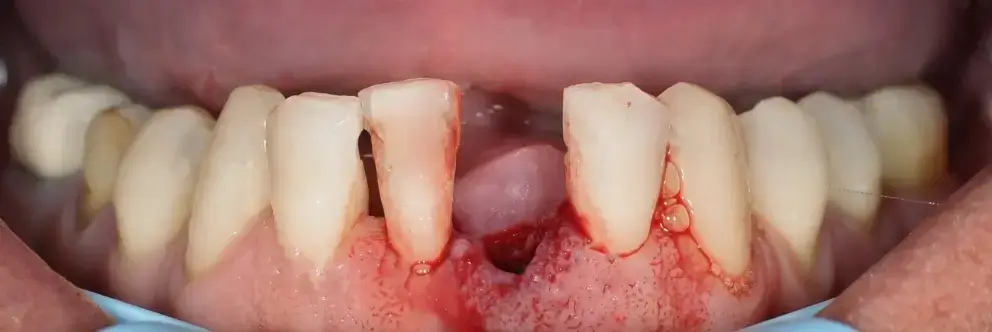

Do your gums bleed when you brush or floss?

That’s not “normal.” It’s the earliest sign of a hidden disease silently spreading inside your mouth.

The Silent Epidemic in Your Gums… And the Breakthrough Dentists Ignore

Nearly 47% of adults over 30 have gum disease, and 1 in 3 suffer from bad breath. Dentists see it every day—yet they keep telling you to “brush more and rinse harder.”